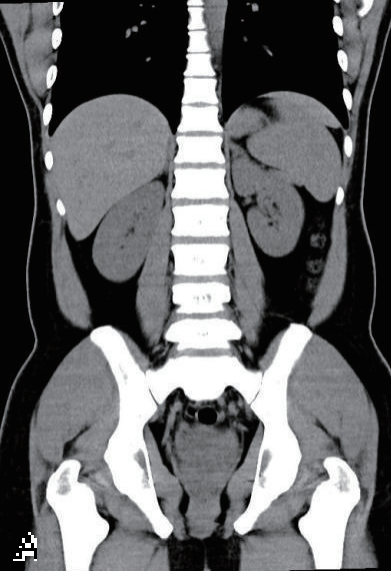

基础信息:患者男,42岁,尿血吸虫虫卵阳性,血清抗体1∶128,尿常规微量红细胞,无明显症状;采用通用泌尿系CT平扫(肾脏至耻骨联合,120kV/150mA,无延迟期,膀胱未充盈)。

影像表现与漏诊原因:双肾大小形态正常、密度均匀,平扫难辨早期间质炎症及肾功能异常;双侧输尿管无扩张增厚,5 mm层厚遗漏黏膜细微病变;膀胱半充盈、黏膜欠光滑,未充盈掩盖早期黏膜增厚,平扫无法识别炎症(图1)。

病情进展:半年后右侧腰痛,复查CT平扫示右肾盂重度扩张、肾实质变薄,右侧输尿管下段增厚狭窄、钙化,膀胱壁钙化,系早期漏诊延误干预。

图1

A:5 mm层厚泌尿系CT平扫冠状位示双肾大小形态正常、密度均匀,双侧输尿管无扩张增厚;

B:5 mm层厚泌尿系CT平扫轴位示膀胱半充盈、黏膜欠光滑